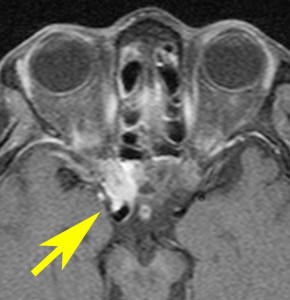

視神経鞘髄膜腫 optic sheath meningioma

眼窩内腫瘍です。視神経を包むし神経鞘から発生して,視神経鞘に沿って進展して増大します。視神経を圧迫してゆっくり症状が出ます。片目の視力が落ちるというのが症状ですが気づかれず発見が遅れることが多いでしょう。眼底検査で,初期には視神経乳頭 optic discの腫れが見られ,視力が悪化していくと視神経萎縮となります。眼底検査で動静脈シャントが見られるのも特徴的で,視力低下と視神経萎縮と併せてHoyt-Spencer triadと言われました。視力がほぼ消失するまで腫瘍が増大すると,眼球が前に押されて,眼球突出 exophhalmus, enophthalmus という症状が出ます。

治療は手術摘出ですが,この腫瘍を摘出するとほぼ確実に片眼の視力を消失します。ですから視力が無くなるまで手術は待機するという考え方が一般的です。数年以上視力があまり低下しないで腫瘍も増大せず経過する患者さんもいます。視力温存目的で治療するなら,視力の良いうちに定位放射線治療を行うべき疾患です。だからといって何でも定位放射線治療をすればよいというものではありません。問題は,視神経管から鞍結節に腫瘍が伸展している例があるということです。ここを放置すると反対側の健常な眼の視力が侵されることになりかねないので慎重に判断します。

比較的急速に視力低下して手術摘出した例

右目が暗いという症状で発症して,眼科では視神経乳頭腫脹とわずかな視野欠損だけで発症した患者さんです。3年間観察されましたが,その間には眼底所見も視力 Vd 1.2 も変化がなかったとの眼科からの報告です。そのすぐ後で患者さん本人は,右目が暗くなる回数が増え、視野狭窄があり軽い眼球突出,まわりがぼやけてますが中心は1.0見える状態との訴えで相談を受けました。主治医の先生の方針では経過観察ということで,まだ視力も良いので私もそうした方がよいと同意したのですが,その後半年くらいで視力が手動弁まで低下してしまいました。眼球運動と右眼球を温存するために腫瘍を摘出しました。

左側は,摘出標本の輪切りの写真です。この部位は腫瘍の発生した部位ではありません。一番外側にみえるのは視神経鞘 optic sheathという膜です。その内側が髄膜腫で,その内側が視神経です。すなわち髄膜腫は,視神経鞘と視神経の間のくも膜下腔を,這うように伝わって増殖伸展しています。このくも膜下腔には視神経への栄養動脈や網膜動脈も入っているので,この腫瘍だけを視神経や細動脈を傷つけずに摘出することはできないのです。

放射線治療をした例

鞍結節部から視神経管を伝わり視神経鞘に伸びていた例です。鞍結節部と視神経管での視神経圧迫があったのでそこを除圧するために摘出したのですが,グレード2の髄膜腫で再発しました。下のMRIは,放射線治療 50Gy/25frしてから5年後の画像です。腫瘍は大きくなっていませんし,右の視力はVd 0.5あり,有用視力といえるほどの視野ではありませんが,視野は上の方で残っています。